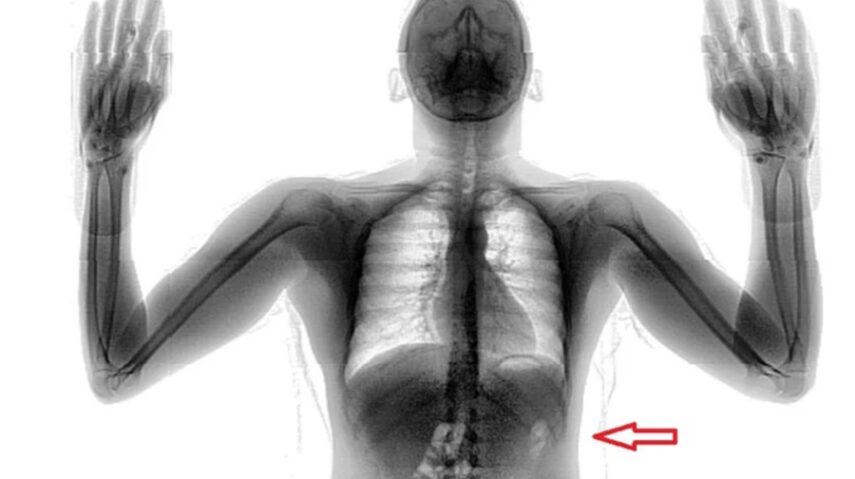

A diretora da unidade prisional, PP Izabel Maria, explicou que a penitenciária é equipada com um scanner semelhante aos utilizados nos aeroportos e que todos que adentram ao estabelecimento são submetidos ao procedimento padrão do sistema penitenciário do RN. Normalmente, o equipamento por si só já inibe as tentativas de entrada de objetos ou substâncias proibidas. Os servidores procuram principalmente drogas e eletrônicos. Mas desta vez, o operador detectou algo estranho dentro do corpo do suspeito, na região do abdômen.

O homem passou duas vezes no aparelho e após ser indagado pelos policiais penais confessou ter engolido a droga. A maconha estava envolta em papel filme (plástico). Foi ingerida no dia anterior, mas ele não revelou o motivo do ato. “Ele foi a unidade prisional para cumprir a sanção disciplinar por faltas no regime semiaberto, onde cumpria prisão domiciliar, e agora acabou preso em flagrante”, confirmou a diretora.